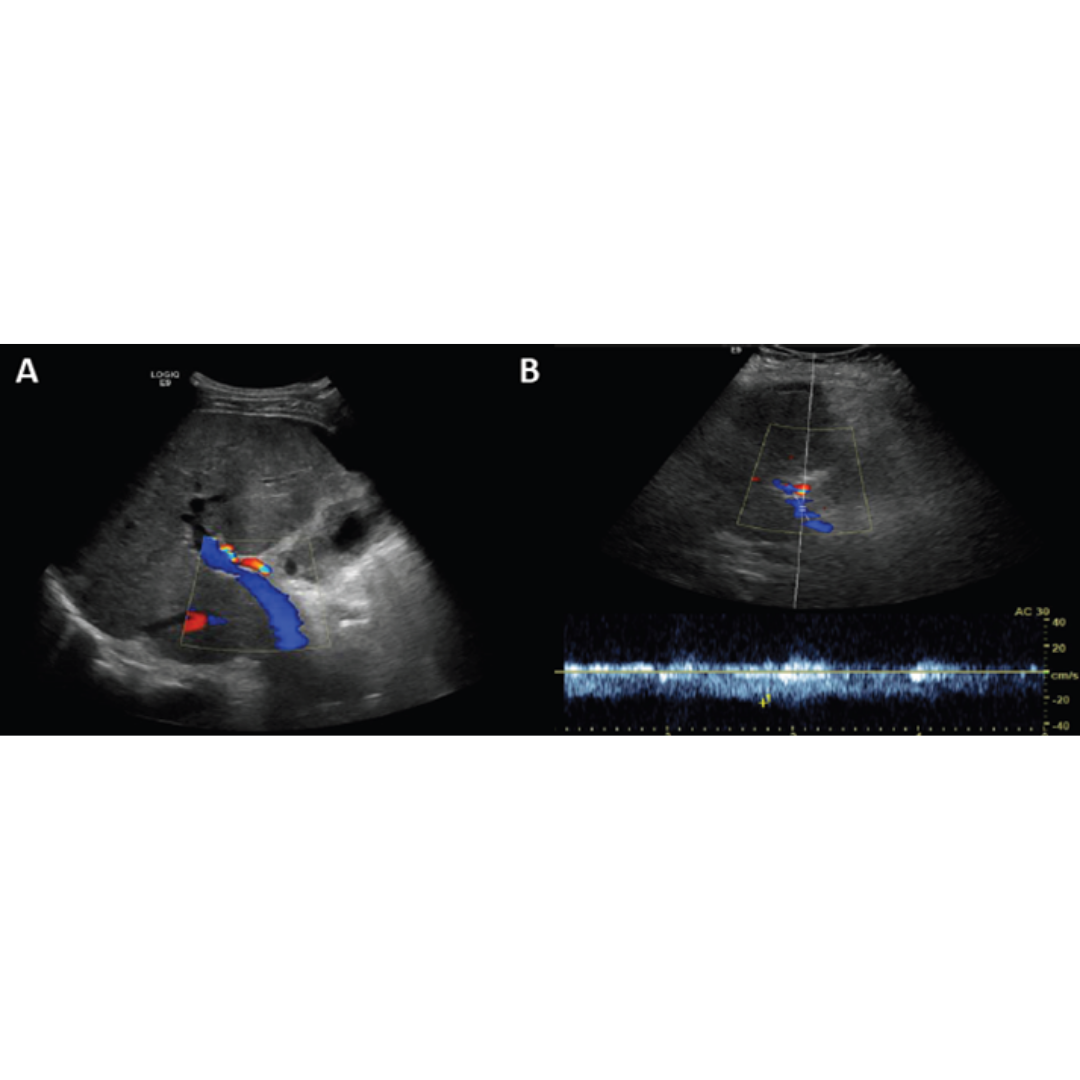

En las venas intrahepáticas al estudio espectral se visualiza un cambio de su morfológica típica trifásica, existe un aplanamiento o incluso morfología pseudoportal viéndose un flujo de aspecto bifásico por consecuencia de la estenosis que generan los nódulos de regeneración (figura 9).

Figura 9: A. Aplanamiento de la onda de la vena hepática media con pérdida del flujo trifásico a flujo bifásico. Flujo trifásico normal de venas suprahepática.